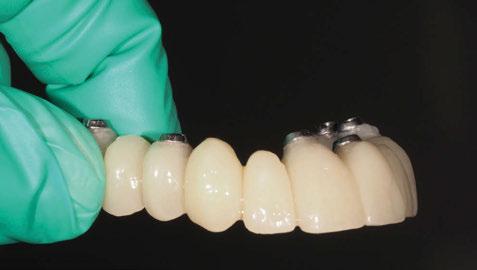

4. Fase protésica provisional

Una vez colocados los pilares provisionales de titanio, se adaptó la férula pick-up modificada y se verificó su correcto asentamiento de los pilares a través de los orificios de ésta. A continuación, se recapturó la férula a los pilares de titanio mediante resina acrílica autopolimerizable (Enamel Temp

Plus®) y, una vez polimerizada, se tomó un registro de mordida, se desatornillaron los pilares y se retiraron de boca. Seguidamente, se atornillaron los análogos verificando que no hubiera movilidad de ningún pilar y se envió al laboratorio para el acabado y pulido final, eliminando todo el soporte y añadiendo un refuerzo metálico por palatino. En boca, se colocaron los tapones de cicatrización de los transepiteliales y se le explicaron las recomendaciones postquirúrgicas y medicación necesaria. Instruimos al laboratorio a dejar los perfiles de emergencia lo más estrechos posibles y los pónticos ovoides entrando unos 3 mm en cada alveolo a fin de preservar la arquitectura gingival presente.

A las 24 horas se citó al paciente nuevamente, se atornilló el provisional en boca y se realizó una

Figura 24. Provisional finalizado tras acabado y pulido en el laboratorio.

Figura 25. Provisional finalizado tras acabado y pulido en el laboratorio.